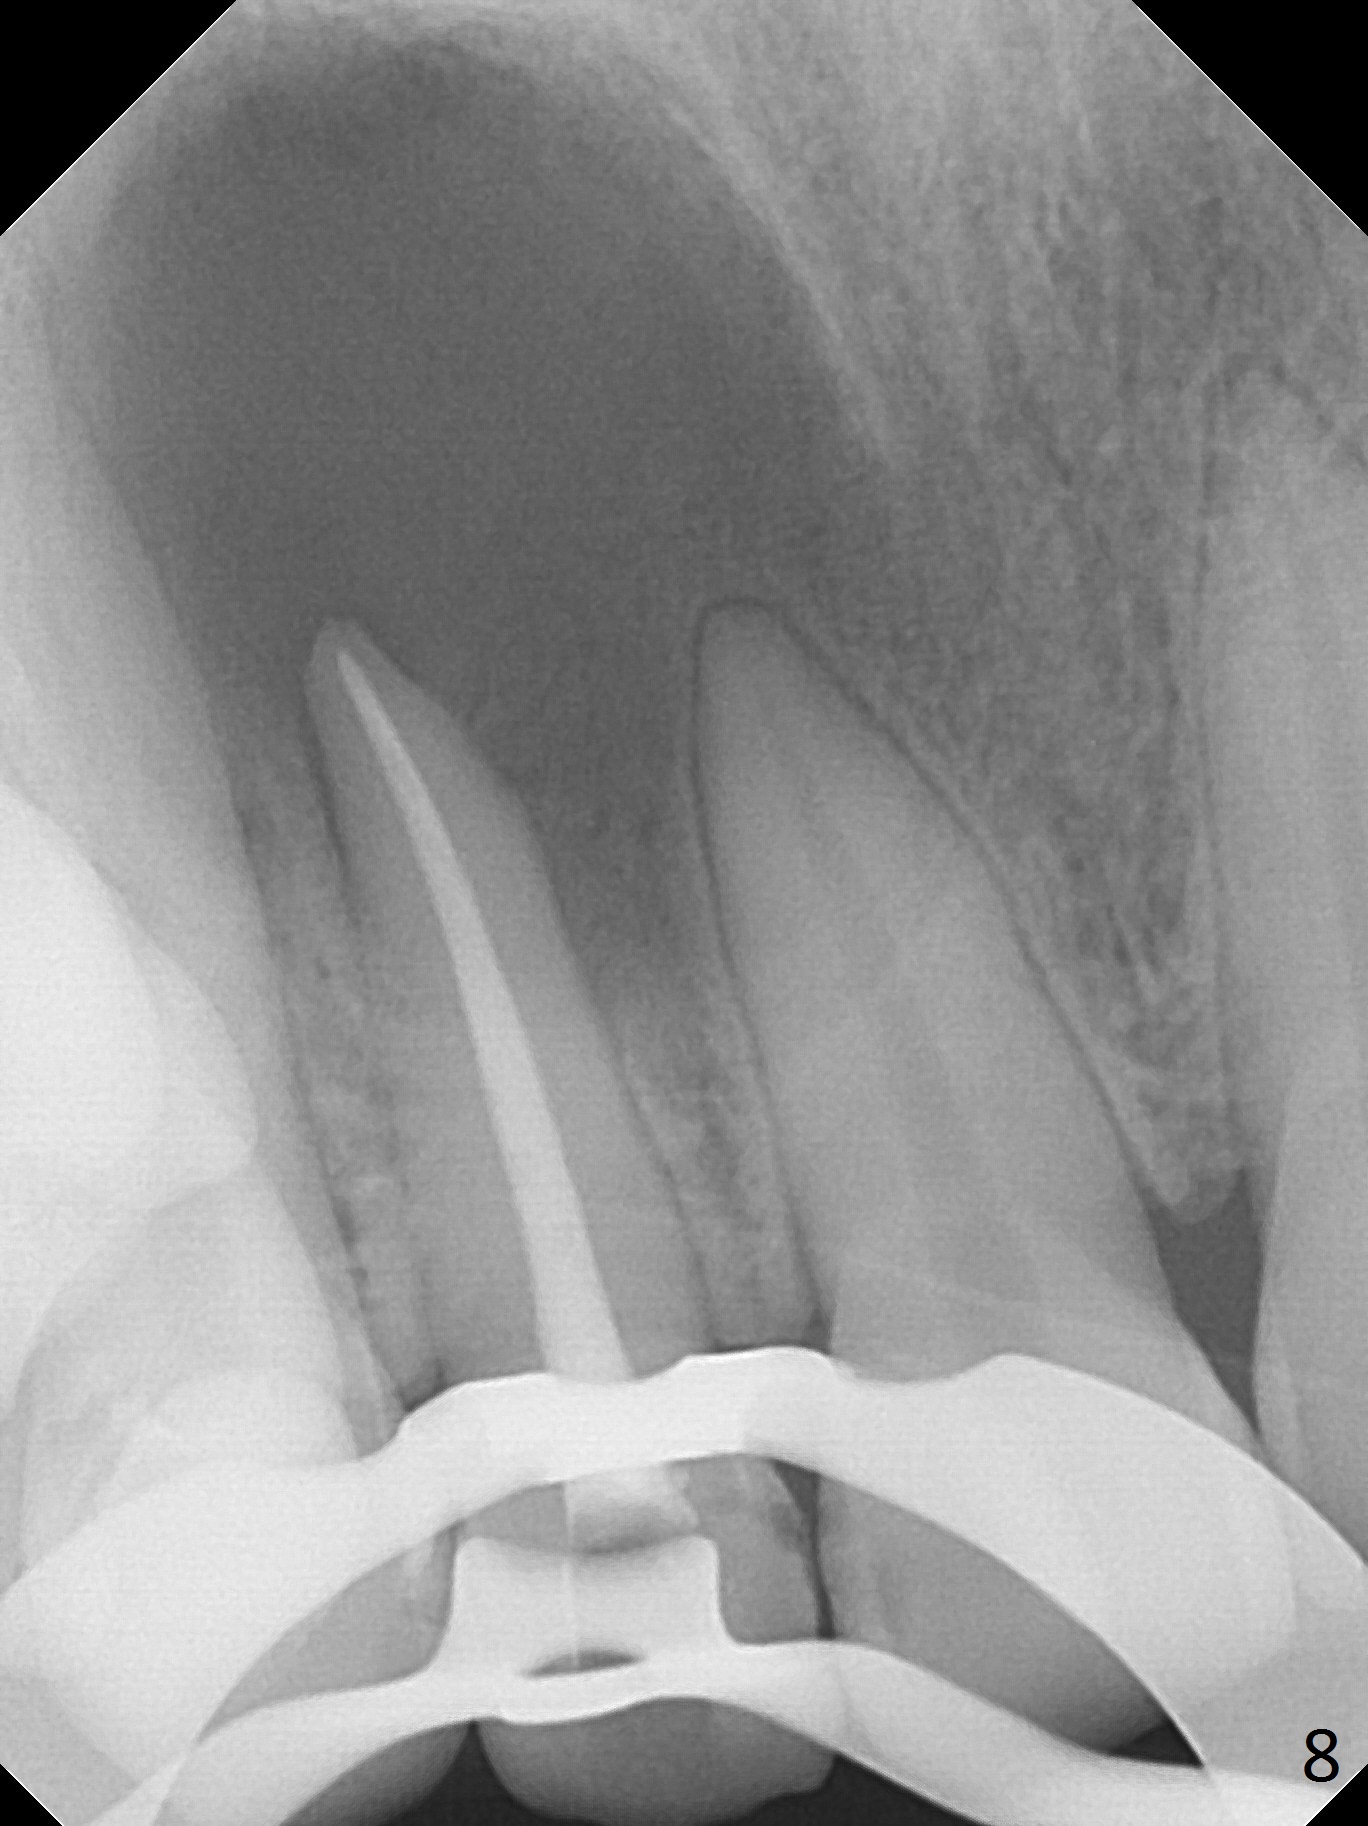

When this patient returns with improvement of symptoms, RCT will be finished. In fact the swelling relapses a month later (Fig.6). After discussion of possible cyst enucleation and increase in debridement from 30/.04 to 40/.06, a master cone of 40/.06 is inserted (Fig.7) and RCT is finished (Fig.8). Although the patient reports relapse of swelling, the palate looks normal and bone density increases 7 months postop (Fig.9). For 14 implant placement, CT is taken 2 years 1 month post RCT (Fig.10,11). Radiolucency is confined to the apex of the tooth #7 (white *). The labial concavities mesial and distal to the left lateral incisor makes radiolucencies (bone loss) look more radiolucent, creating globumaxillary cyst image. The globumaxillary cyst is a terminology for its shape. It does not mean congenital in nature. The treatment is dependent upon vitality test of the involved teeth.